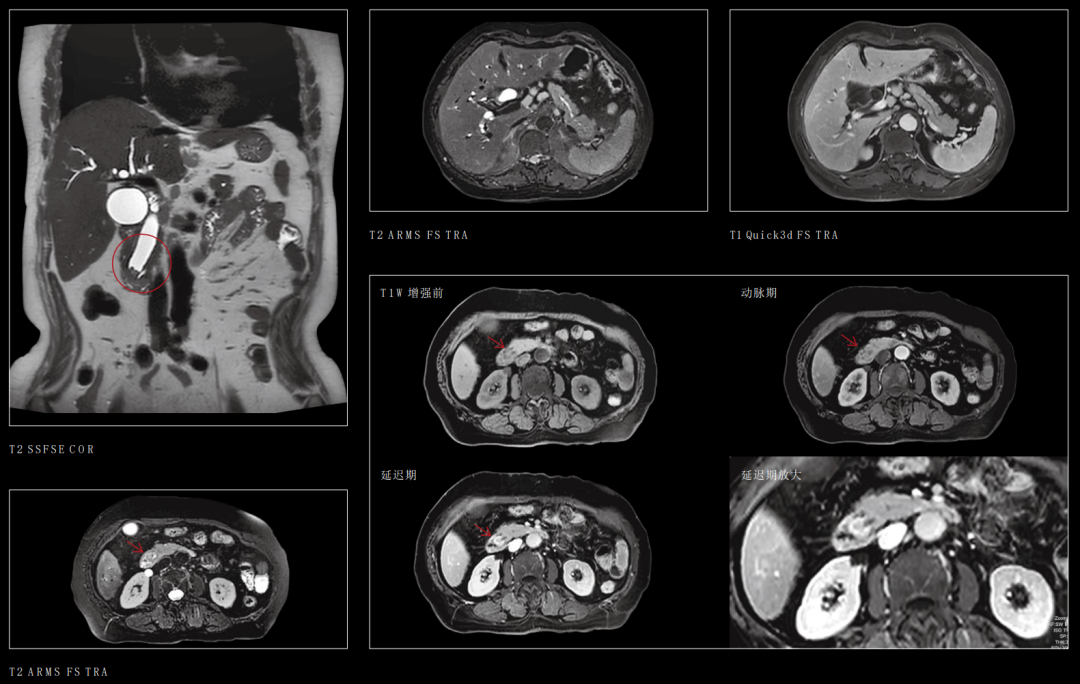

3、腹部器官

腹部良、恶性肿瘤的诊断与鉴别诊断,可以进行脂肪定量成像、磁敏感成像、腹部大血管高分辨率成像。

联影磁共振怎么样【三级医院创建 • 技术装备提升】再添医学影像“利器”——我院引进联影uMR870  3.0T磁共振_https://www.jmylbn.com_新闻资讯_第20张

十二指肠壶腹部占位

肾上腺常规成像

联影磁共振怎么样【三级医院创建 • 技术装备提升】再添医学影像“利器”——我院引进联影uMR870  3.0T磁共振_https://www.jmylbn.com_新闻资讯_第26张

乳腺常规动态增强